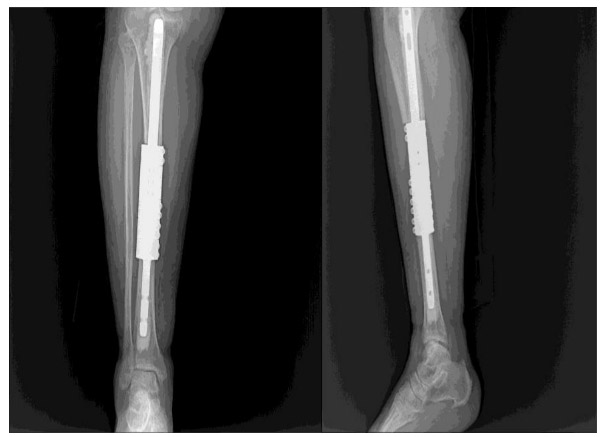

Post-surgery: Application of cemented tumor prosthesis to replace the removed tumor bone